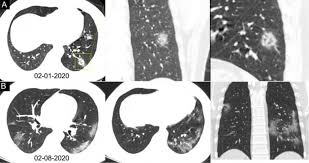

Infection Au Covid 19 Quelle Imagerie Le Generaliste

Infection Au Covid 19 Quelle Imagerie Le Generaliste from static5.legeneraliste.fr